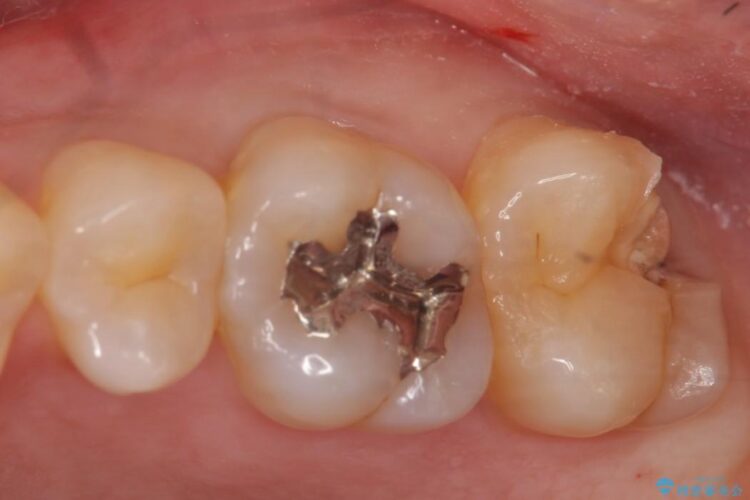

上顎左の一番奥の歯が深い虫歯になって脆くなり、更にその状態に強く噛みしめたわけではない通常の咬合力が加わったことで歯が欠けてしまっていました。

今回は一番奥の歯という位置と、噛み合わせ、清掃状態を加味して適合の高く長持ちするゴールドインレーにて治療することとしました。